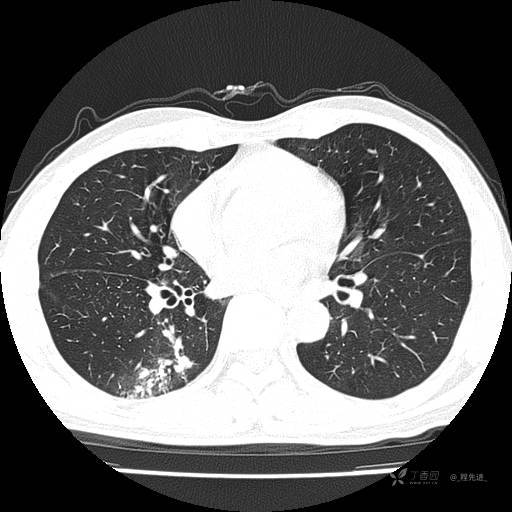

2月特别精彩病例|咳嗽、咳痰20余天,典型病例分享【结果已公布】

呱呱叫了 等 2 位达人已点赞患者性别:男

患者年龄:51岁

主诉:咳嗽、咳痰20余天

简要病史:20余天前开始出现咳嗽、咳痰症状,阵发性刺激性咳,白色粘痰,不易咳出,无发热,无咯血,无恶心、呕吐等不适,未诊治,咳嗽、咳痰症状持续存在。

体格检查:T:36.3 ℃ P:79 次/分 R:20 次/分 BP:128/64 mmHg,神志清楚,呼吸平稳,双肺呼吸音粗,右下肺闻及细湿性啰音。心率79次/分,节律整齐,各瓣膜听诊区未闻及病理性杂音。腹部未见异常,双下肢无水肿。

辅助检查:我院门诊胸部CT示:如下。心电图:窦性心律;正常心电图。